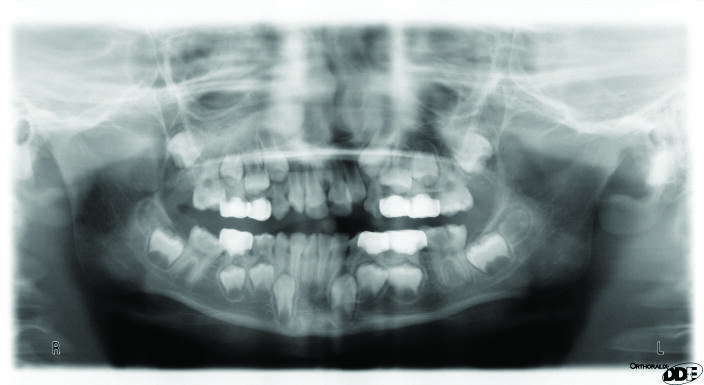

Ectopic eruption of the first permanent molar occurs due to the abnormal mesioangular eruption path of the molar resulting in an impaction at the distal prominence of the primary second molar’s crown. It can be suspected if asymmetric eruption is observed or if the mesial marginal ridge is noted to be under the distal prominence of the second primary molar. Ectopic eruption can be diagnosed from bitewings or panoramic radiographs, Fig 1, 2. The prevalence of this condition is reported to be up to 0.75%1. The ectopic eruption is more common in cleft lip and palate patients1.

Figure 1: A panoramic radiograph showing ectopically erupted upper right and lower right first permanent molars.